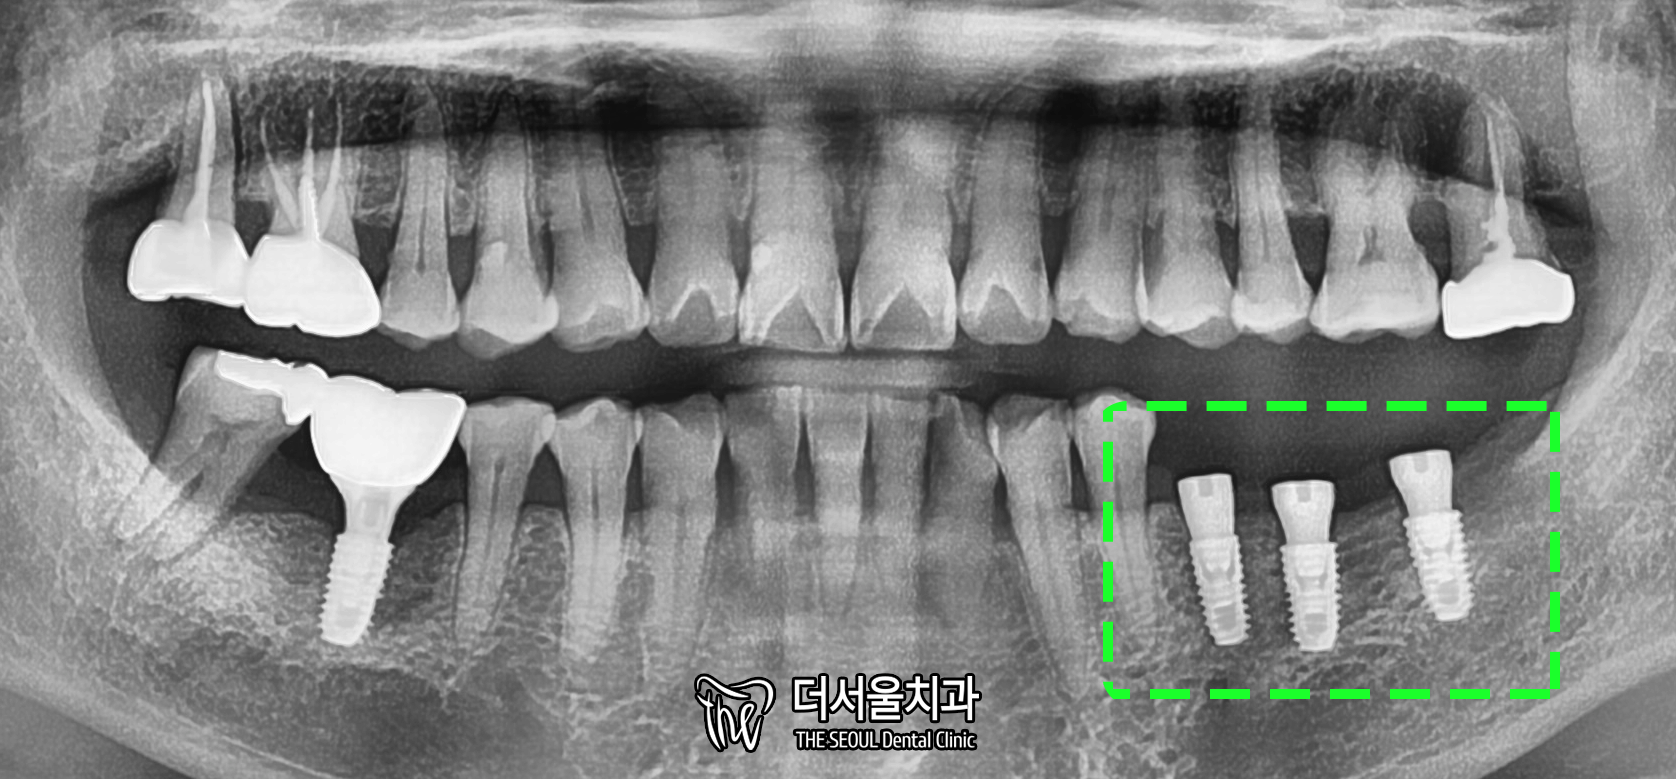

6. 40번대 완료

이렇게 성남 치과 의원에서

잃어버린 어금니 4개를 새롭게 채워드렸습니다.

다른 병원에서는 틀니를 해야 된다 했는데요.

이렇게 뼈이식과 임플란트를 심으면

충분히 관리하기 편한데 말이죠.

환자분 또한 윗니와 잘 맞닿는 점,

음식을 편하게 먹을 수 있다는 점이 좋다하시네요.

이제는 편하게 일상 생활을 하실 수 있습니다.

엑스레이를 찍어서

확실하게 잘 붙었는지 확인해줍니다.

튼튼하게 잘 식립되었네요. ^^

이렇게 모든 수술 과정은 다 끝났습니다.